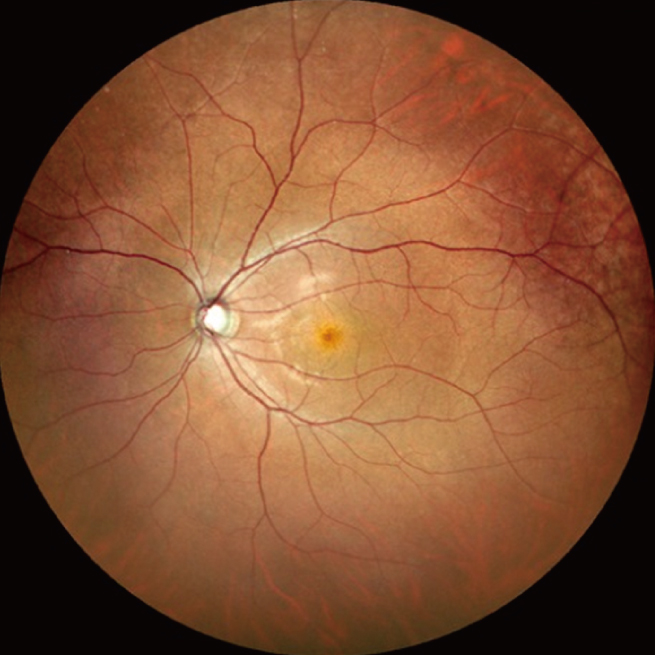

・眼底カラー写真

4Kの高解像度な広角カラーSLOを用いて、視神経や黄斑部などの狭角撮影はもちろん、網膜の端の方まで散瞳しない状態で広角に撮影することができます。糖尿病網膜症の患者さんなどは、散瞳しなくても眼底の状態を調べることができます。車での来院も可能です。今後、まったく散瞳しなくてもいいというわけではありませんが、かなりその頻度は減らせると思います。